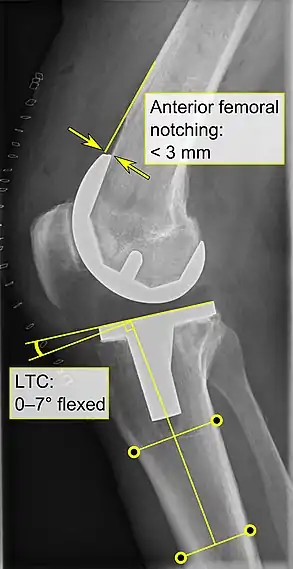

Knee replacement is routinely evaluated by X-ray, including the following measures:

- FFC: frontal femoral component angle. It is typically regarded as optimal when being 2–7° in valgus.[56]

- FTC: frontal tibial component angle, which is regarded as optimal when being at a right angle. A varus position of more than 3° has generally been found to increase the failure rate of the prosthesis.[56]

- Anterior femoral notching (the femoral component causing reduced thickness of the distal femur anteriorly), seems to cause an increased risk of fractures when exceeding about 3 mm.[57]

- LTC: lateral (or sagittal) tibial component angle, which is ideally positioned so that the tibia is 0–7° flexed compared to at a right angle with the tibial plate.[56]